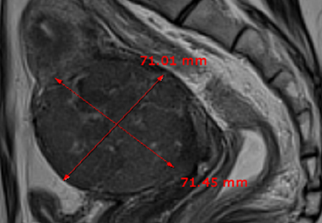

자궁근종 비수술 하이푸 치료 후 임신분만사례입니다. 아직 자녀가 없으신 분으로 복부에 만져지는 증상으로 자궁근종 하이푸 치료를 위해 내원하였습니다. 하이푸 시술전 MRI 사진상 자궁은 7.5cm 크기로 자궁전벽의 ...